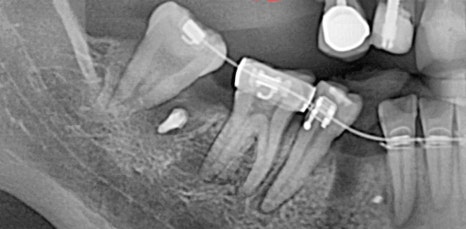

하지만 임플란트 시술을 튼튼하고 안전하게 하기 위해서는 무엇보다 잇몸뼈의 양, 두께 즉, 잇몸 상태가 매우 중요한 부분이었어요. 뿌리 역할을 하는 픽스처의 길이는 다양한 사이즈가 있지만 평균적으로 최소 8mm 이상이므로 잇몸 뼈의 길이가 8mm가 되지 않는 상태로 임플란트를 식립하게 된다면 픽스처가 잇몸을 뚫고 나가게 되어 구멍이 생기고 고정이 되기 어려웠어요. 그렇기 때문에 잇몸 뼈의 양이 부족하면 뼈 이식을 동반한 임플란트 시술이 필요했어요.

특히 위쪽 어금니 쪽이 상실 되어 임플란트 시술을 진행해야 하는데 잇몸 뼈가 부족한 상태라면 추가적으로 상악동거상술을 함께 진행해야 했어요. 상악동이란 코 양옆에 위치하고 있으며 뼈 속에 비어 있는 공기 주머니로 두개골의 무게를 줄여주는 곳이었어요. 상악동은 아주 얇은 막으로 둘러 쌓여 있으며 상악 쪽의 잇몸 뼈가 부족한 상태로 임플란트를 식립 하게 된다면 상악동 막이 찢어지거나 천공이 생길 수 있었어요.

상악동에 천공이 생기게 된다면 염증으로 인해 부작용이 생길 수 있었어요. 그렇기 때문에 환자 개개인마다 크기와 위치가 모두 다른 상악동의 위치와 잇몸 뼈의 두께를 정확히 파악하는 것이 중요했어요. 정밀 검사 후 임플란트를 식립 하기에 잇몸 뼈의 양이 부족하다는 진단이 나오게 된다면 얇은 상악동 막을 들어올려 준 후 필요한만큼의 뼈 이식을 진행해 주는 방법이 상악동거상술이었어요.

신논현역임플란트에서 말하는 상악동거상술은 치조정접근법과 측방접근법인 두가지 방법으로 진행할 수 있었어요. 남아 있는 잇몸 뼈의 양에 따라 이식 해야 하는 양이 달라지고 그로 인해 상악동에 접근 하는 방법을 기준으로 두가지 방법은 나눠 지고 있었어요. 먼저 치조정접근법은 잇몸 뼈가 4-8mm 정도 확보 되었을 때 사용하는 방법으로 치아가 상실 된 위치의 잇몸에 작은 구멍을 뚫어 준 뒤 그 구멍을 통해 상악동 막을 들어 올린 후 뼈 이식을 진행하는 방법이었어요.

작은 절개 범위와 뼈 이식 양이 많지 않기 때문에 수술 시간이 짧고 통증과 붓기도 적으며 회복 속도 또한 측방접근법에 비해 빠른 편이었어요. 반면 측방접근법은 잇몸 뼈가 4mm 이하로 많은 양의 잇몸 뼈를 이식 해야 할 때 필요한 방법이었어요. 잇몸 측면에서 큰 창 모양으로 절개 후 접근하는 방법으로 수술시간이 길고 붓기, 통증이 큰 편으로 회복 속도 또한 더딘 편이었어요.

이러한 구강 상태를 확인하기 위해서는 여러가지 디지털 입체 장비를 통해 정밀 검사를 진행한 후 정확히 파악하는 것이 중요하며 그에 맞춰 적합한 방법으로 진단한 후 체계적으로 치료 계획을 수립 해야 했어요. 의료진의 진단과 시술 경험에 따라 치료 결과는 크게 달라질 수 있기 때문에 상악동거상술을 동반한 임플란트 시술을 안전하고 성공적으로 마치기 위해서는 치과를 선택할 때 꼼꼼히 따져본 후 치료를 시작하는 것이 바람직한 방법이었어요.

신논현역임플란트에서는 3D 구강스캐너와 CT 등 다양한 전문 장비로 구강상태를 정밀하게 입체적으로 확인하고 환자분과 상담을 통해 상악동거상술의 치료 계획을 세우고 있었어요. 상악동거상술은 치과 치료 중에서도 난이도가 높은 치료에 속하기 때문에 환자분께서는 부담스럽고 두려우실 수 있었어요. 무턱대고 당장 치료를 시작하기 보다는 신논현역임플란트 잘하는 아름드리치과에서는 1:1 맞춤치료를 진행하며 환자분들과 충분한 상담을 통해 궁금증을 해결 해 드리고 통증과 부작용에 대한 우려를 덜어 드린 후 안심하고 진료 받을 수 있도록 의사소통을 활발히 하며 언제나 환자분을 우선으로 생각하며 진료하고 있었어요. 또한 얇은 상악동막이 찢어지거나 구멍이 나지 않도록 섬세하고 전문적인 실력이 뒷받침되어야 상악동거상술의 부작용을 최소화 할 수 있었어요.